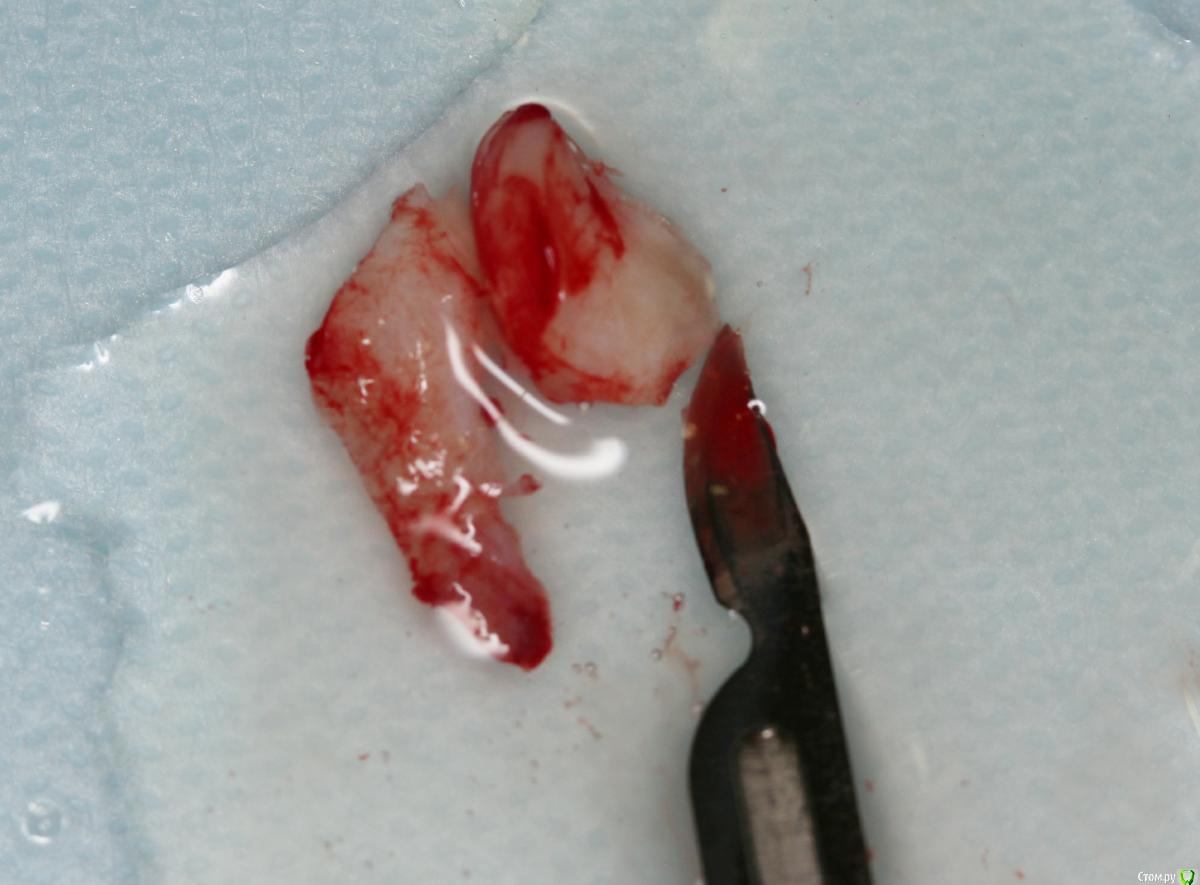

Dmitry DK Опубликовано 10 сентября, 2019 Поделиться Опубликовано 10 сентября, 2019 Фотопротокол к сожалению не полный, но ничего особенного и не проводилось. 1) Открытый синус, удален пломбировочный материал из пазухи, уложен 1 г Bio-oss 2) через 6 мес имплантация Straumann SP 4.1\10 Результат через год 9 Ссылка на комментарий